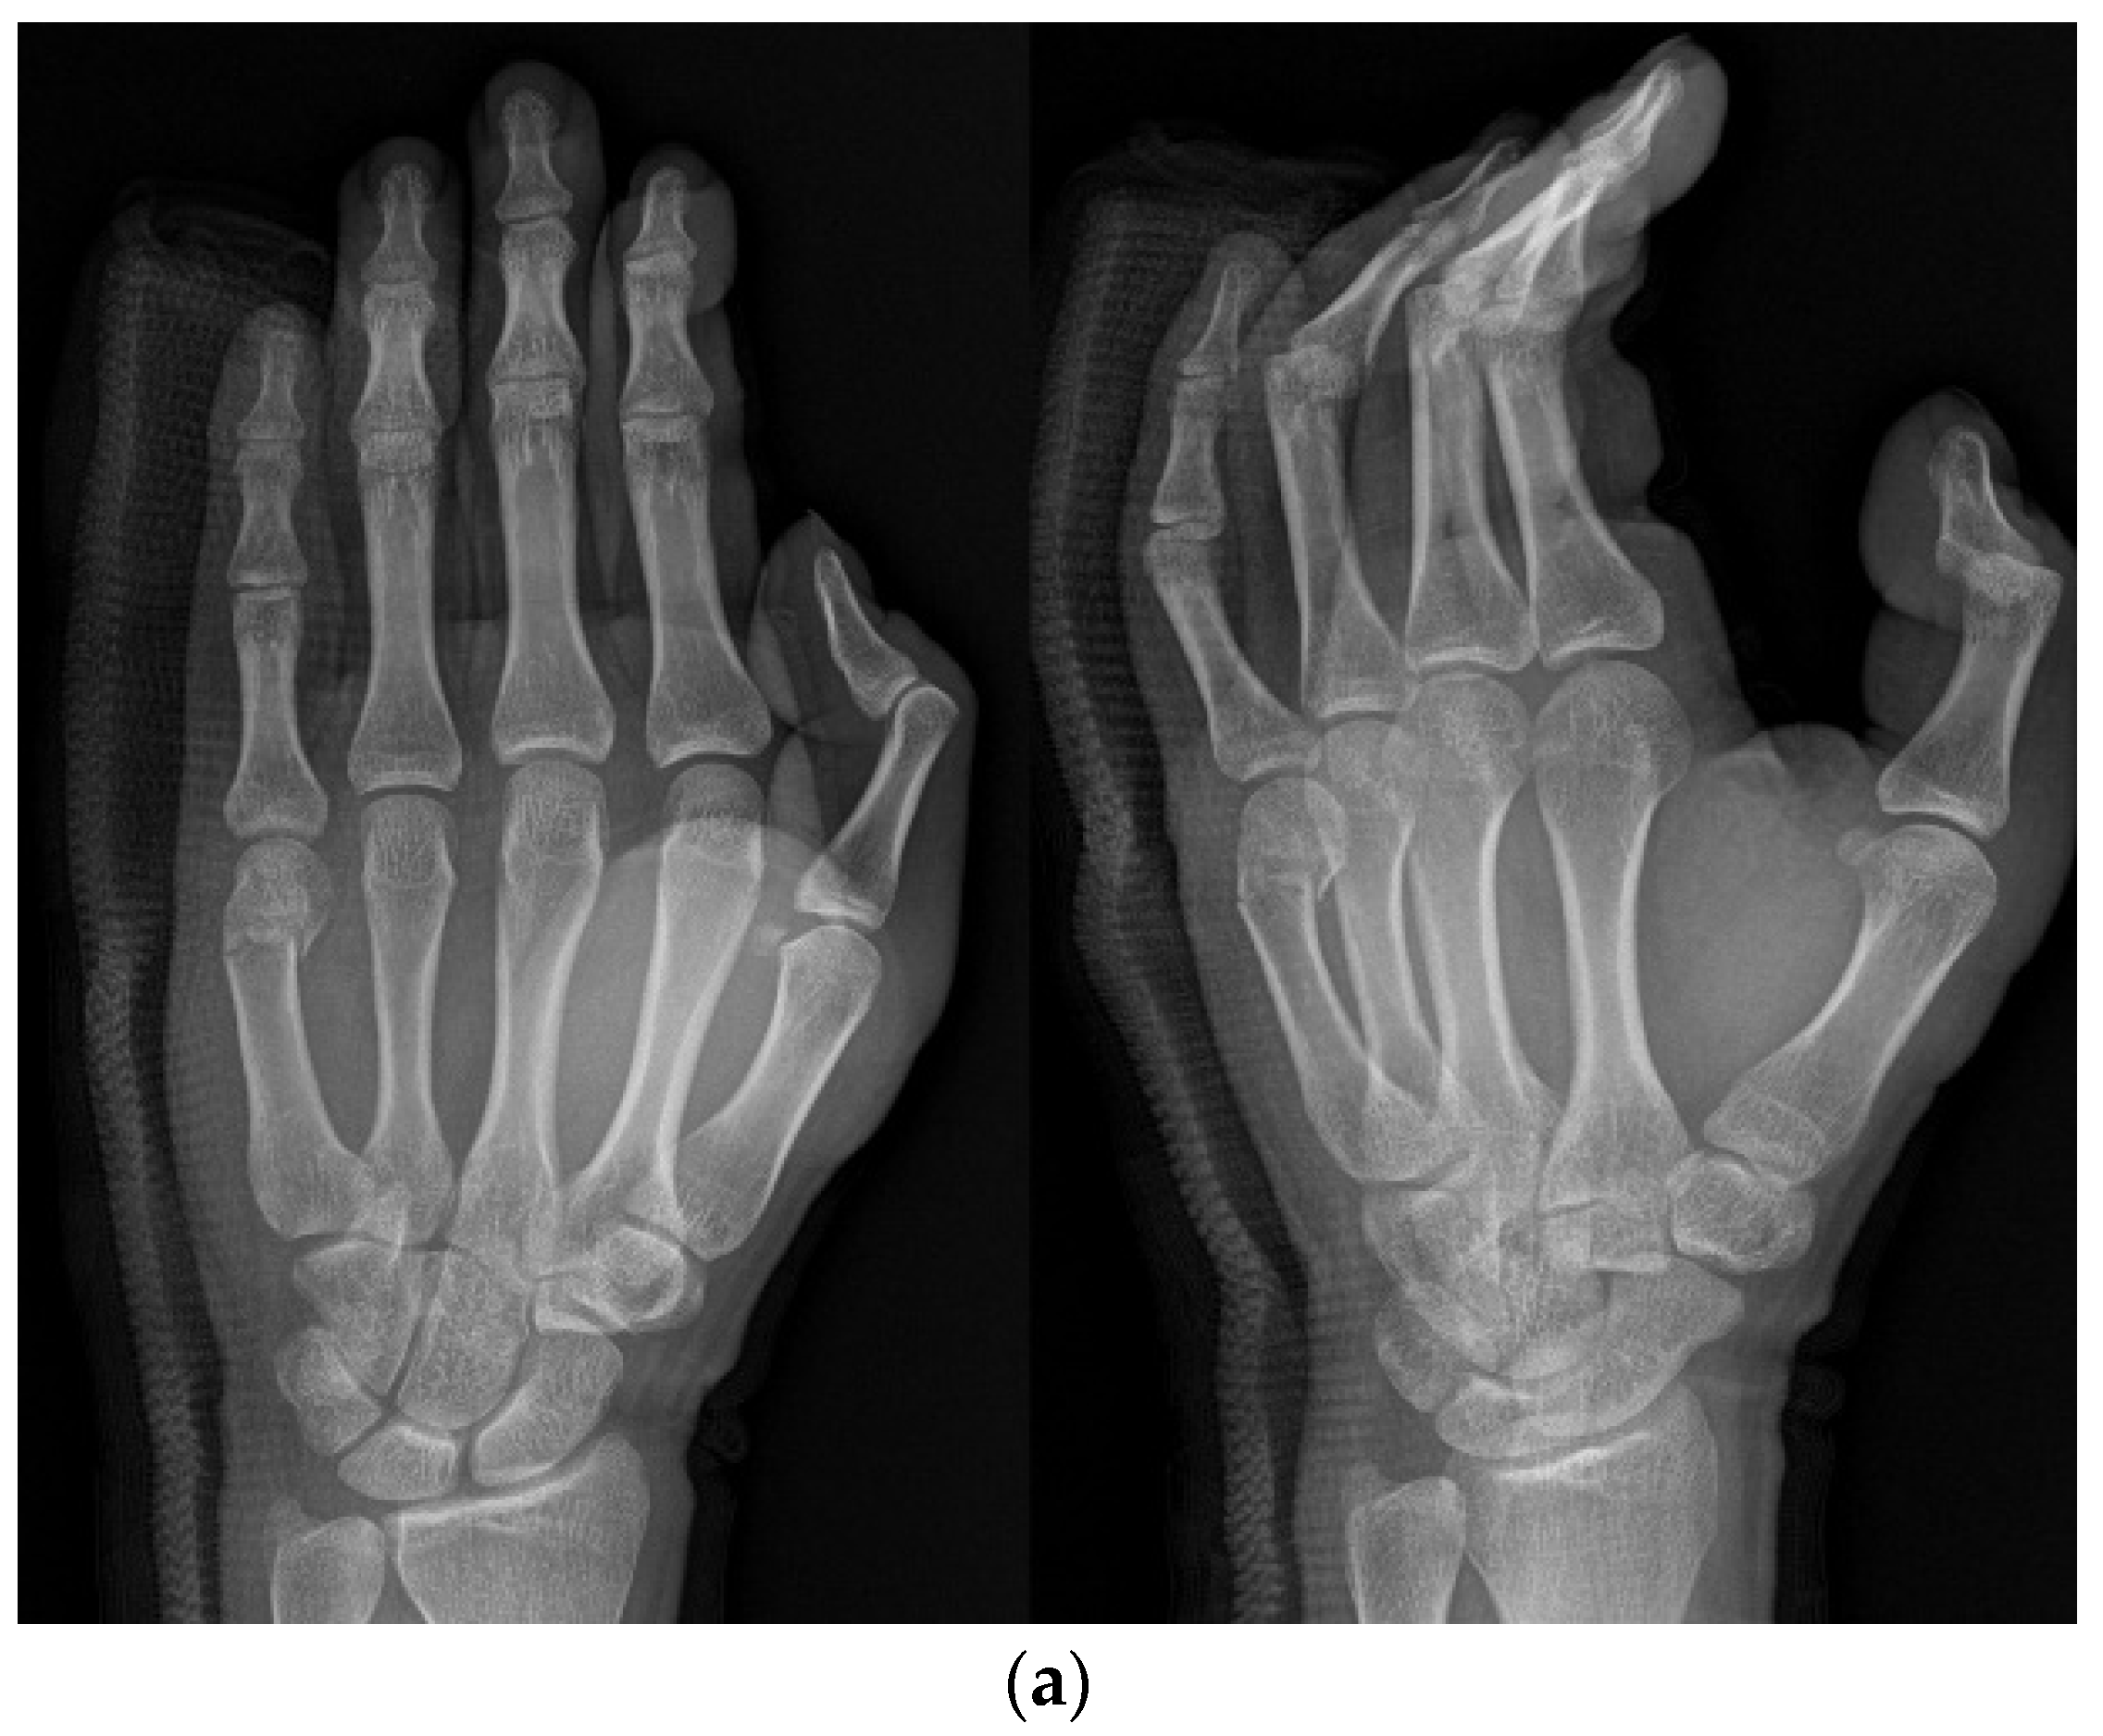

2.2. Methods

2.3. Surgical Technique